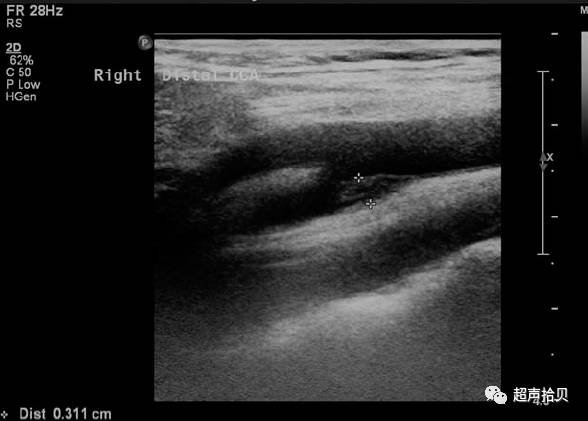

图1.男,37岁,右侧颈部疼痛部位,右侧颈总动脉纵切面(CCA)的分叉处颈动脉后方病变;